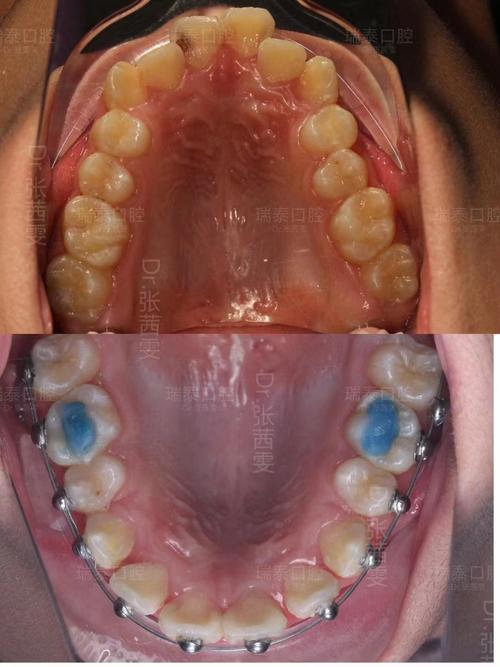

高端连锁品牌如瑞尔齿科、马泷齿科,主打“国际化服务”和“数字化矫正”,瑞尔齿科引进全套德国数字化设备,包括口内扫描仪、CBCT及3D矫正方案模拟系统,能精准预测矫正后的牙齿排列和面部变化,提供隐适美、时代天使等全系列隐形矫正,服务细节贴心,如一对一客服陪同、定期口腔清洁等,但价格较高,通常在3万-6万元,马泷齿科则以舌侧矫正见长,将托槽隐藏在牙齿内侧,完全隐形,适合对美观要求极高的职场人士,但技术难度大,对医生经验要求高,费用可达5万-8万元。